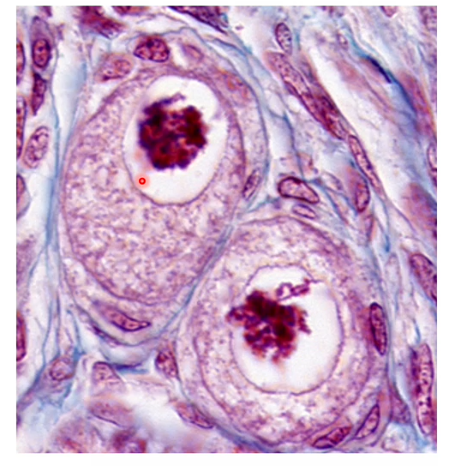

on voit en regard, un primordial qui est entrain de se différencier

Mais je croyais qu’on ne voyait pas les follicules primordiaux donc ça serait plutôt un primaire en cours de différenciation ?

Si on a une image avec cette phrase dans l’item on compte vrai le on voit un primordial ??

Je sais que ça avait l’objet d’un post l’année dernière mais du coup on retient que sur une coupe Histo on peut voir et distinguer un folliculaire primordial d’un primaire ?